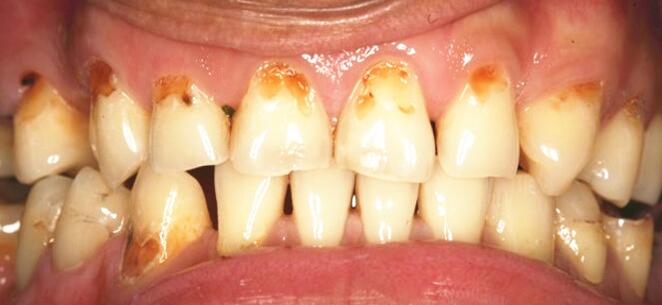

甚至于有些颈部龋齿患者,也“妄想”通过洗牙变白。

多发性颈部龋

我们洗牙后,只能去除牙石这些“脏东西”,露出你原本就存在的“不好看”的牙齿表面!

不可能把你的牙“变”白!!